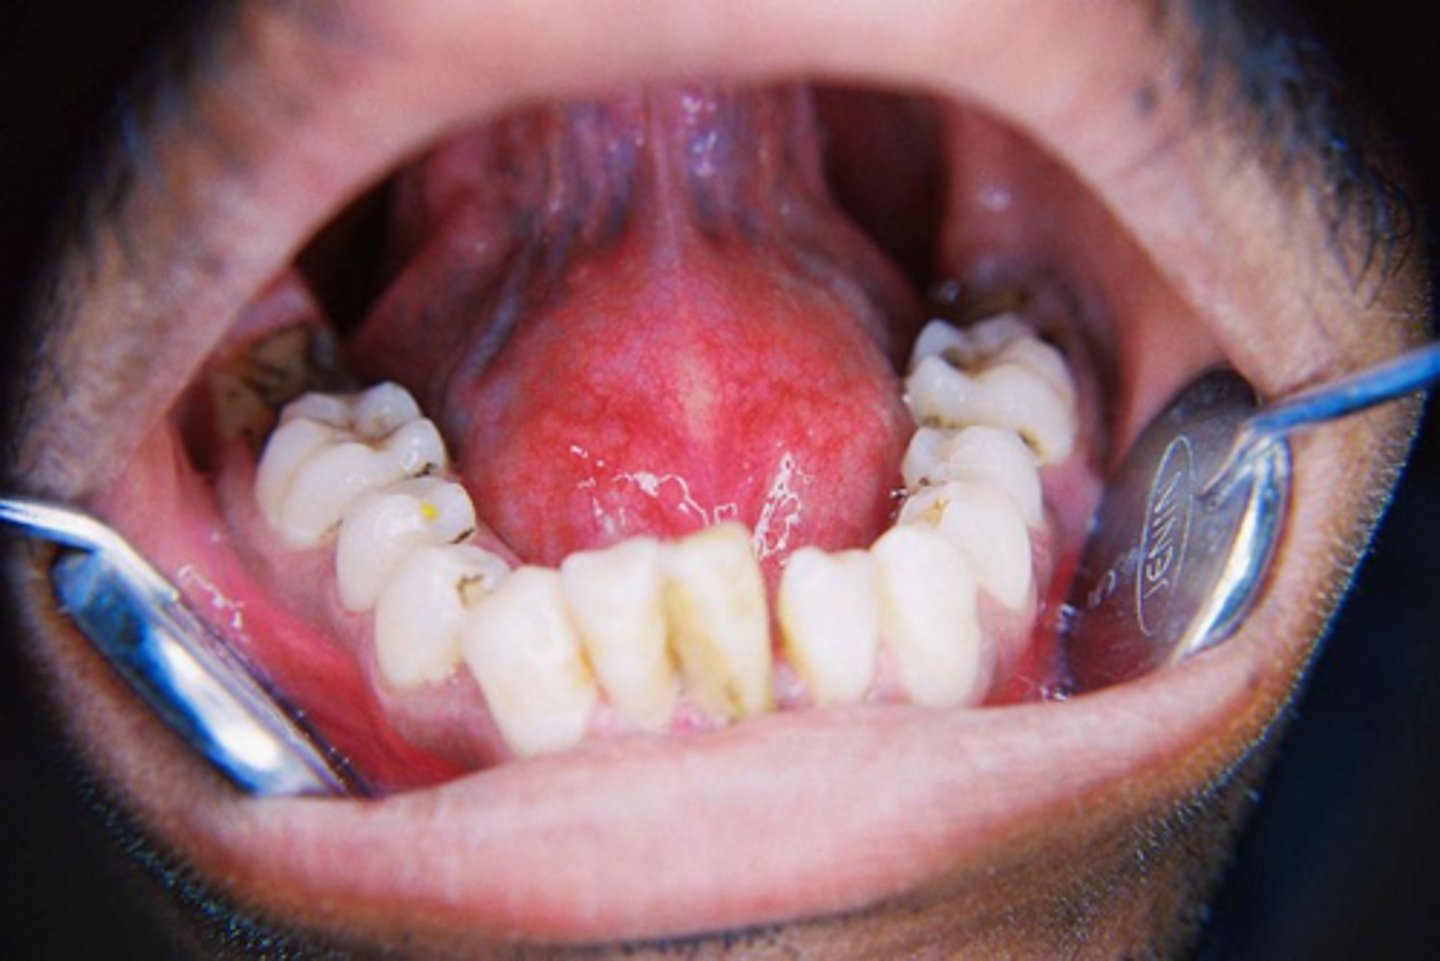

Multiple grayish-white mucosal patches ar present throughout the oral cavity.

secondary syphillis